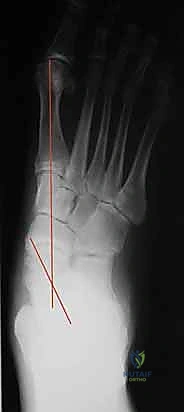

* الأشعة السينية (X-rays) أثناء الوقوف: صور بالأشعة السينية للقدم والكاحل أثناء تحمل الوزن (الوقوف). يتم قياس زوايا محددة (مثل زاوية ميري Meary's angle، وزاوية التغطية الزورقية الكاحلية Talonavicular coverage angle) لتقييم درجة الانهيار العظمي بدقة هندسية.